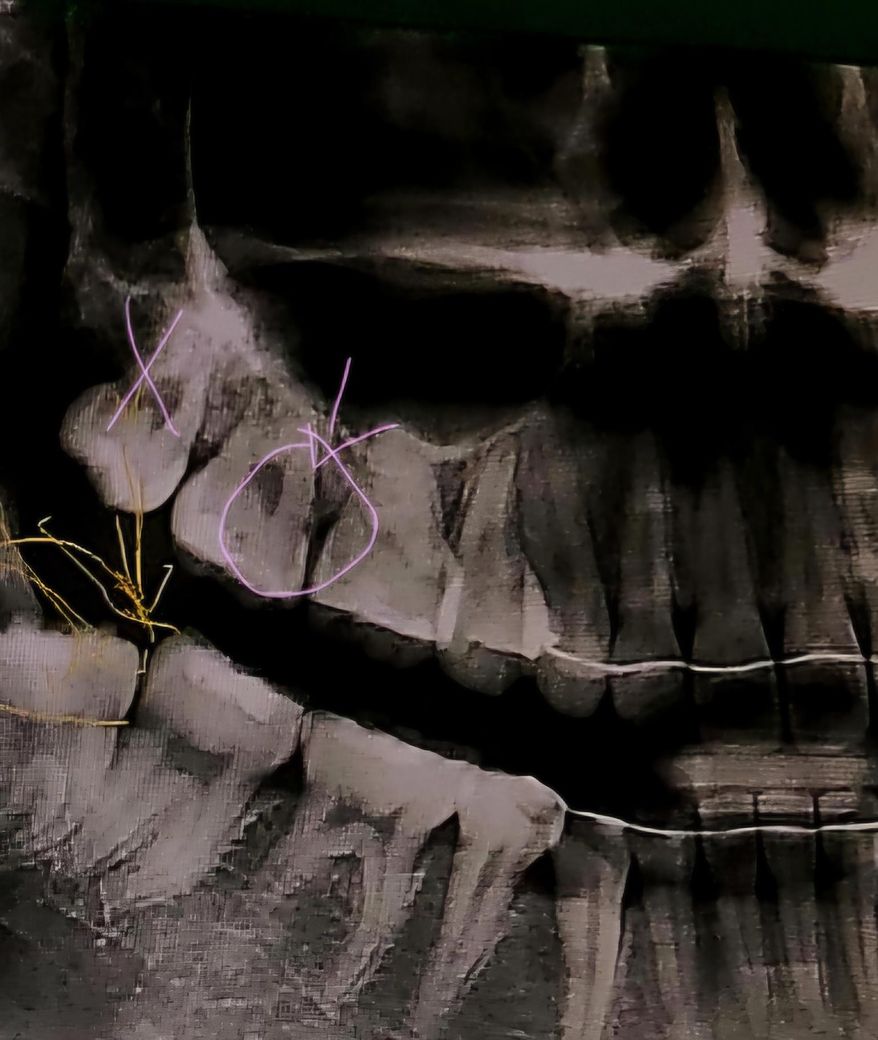

충치 엑스레인 사진 좀 봐주세요 ㅠㅠㅠ

윗 사진은 옛날에 찍은 거구요 아래 사진은 최근입니다.

최근 치과를 갔을 때 (윗사진 찍은 치과와 다른 치과) 인레이나 신경치료 진단을 받았습니다.

통증이 없었어서 예전 사진을 보니까 예전 사진에도 검은 점이 보이네요.. 위치는 다르지만ㅠ

진행이 안 된 걸까요? 충치 치료 해야 하는 건가요? 아님 인터넷에서 본 사례처럼 레진 안에 검정색 물질을 넣어놓고 떼워서 충치처럼 보이는 걸까요?

x친 치아는 제거한 사랑니입니다

엑스레이 상으로는 치아 인접면에 충치가 있는것같습니다. 인레이 치료를 하시거나 충치가 깊으면 신경치료를 하셔야될수도 잇을것같습니다.

사진으로 봤을 경우에는 이전에 충전 치료를 한 재료 아래로 충치가 있는 것으로 보입니다. 충치가 있다면 해당 부위에 빈 공간이 생기게 되어 이물질이 끼게 되고 충치가 진행될 수 있습니다. 충치가 있다면 충치를 치료하는 것이 좋을 수 있습니다.

1. 말씀하신 "레진 안에 검정색 물질을 넣어놓고" 는 일반적으로 통용되지 않는 치료 방식입니다.

2. 불투과성 재료로 떼우면 무조건 x-ray 상에서 밝은 흰색으로 보입니다. 검게 보이는 재료는 없습니다.

3. 최근에 찍은 엑스레이를 보면 레진으로 떼운 것 하방으로 이차충치가 의심되고 워낙 충치가 깊기 때문에 신경치료 가능성이 언급된 것 같습니다.